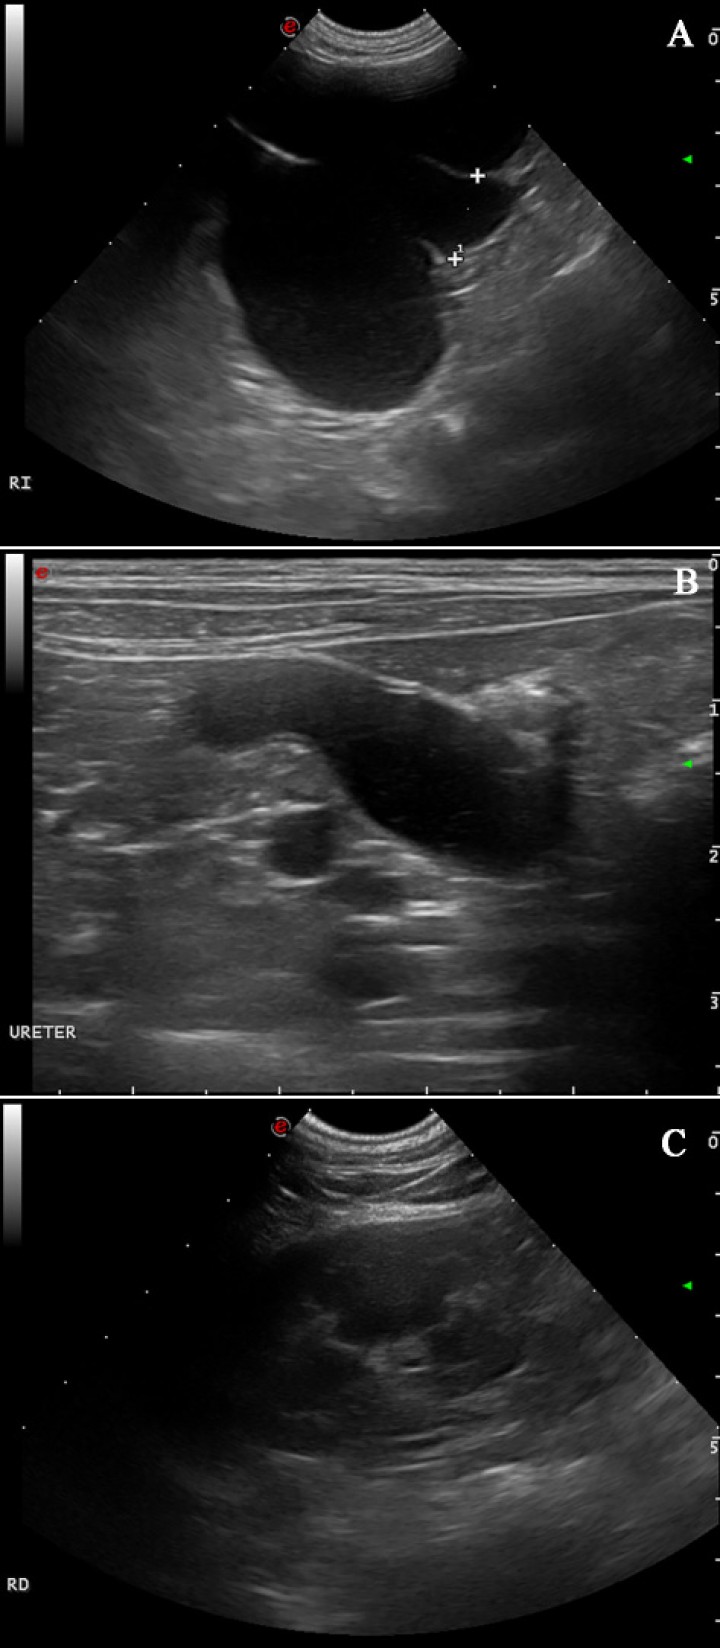

Un año más tarde, la paciente fue remitida para un examen ecográfico porque presentaba polaquiuria y en la analítica sanguínea unos valores de creatinina levemente aumentados (1,53 mg/dl; rango normal: 0,7 a 1,4 mg/dl). El resto de los parámetros se encontraron dentro de los valores de referencia. En la evaluación ecográfica se visualizó una masa de características similares a la observada un año antes y en el mismo lugar (Fig. 1B) de 2,5 cm de diámetro. Además, la pelvis renal y divertículos del riñón izquierdo se encontraban marcadamente dilatados por líquido anecogénico con una mínima remanencia de la corteza renal (Fig. 2A). El uréter ipsilateral también estaba severamente dilatado en todo su trayecto con contenido anecogénico, midiendo 1,65 cm de diámetro y pudiendo seguir su recorrido hasta la masa en la que se encontraba involucrado (Fig. 2B). El riñón derecho presentaba un aspecto normal (Fig. 2C). El diagnóstico presuntivo fue de hidronefrosis e hidrouréter izquierdo severo debido a compresión del uréter izquierdo por parte de un granuloma por cuerpo extraño en el muñón uterino.

<p>Imágenes ecográficas al año de la primera presentación. (<strong>A</strong>) Hidronefrosis del riñón izquierdo: se observa una marcada dilatación de la pelvis renal y divertículos del riñón izquierdo por líquido anecogénico con una mínima remanencia de la corteza renal. (<strong>B</strong>) Severo hidrouréter izquierdo con contenido líquido anecogénico. (<strong>C</strong>) Riñón derecho de aspecto normal.</p>

Imágenes ecográficas al año de la primera presentación. (A) Hidronefrosis del riñón izquierdo: se observa una marcada dilatación de la pelvis renal y divertículos del riñón izquierdo por líquido anecogénico con una mínima remanencia de la corteza renal. (B) Severo hidrouréter izquierdo con contenido líquido anecogénico. (C) Riñón derecho de aspecto normal.